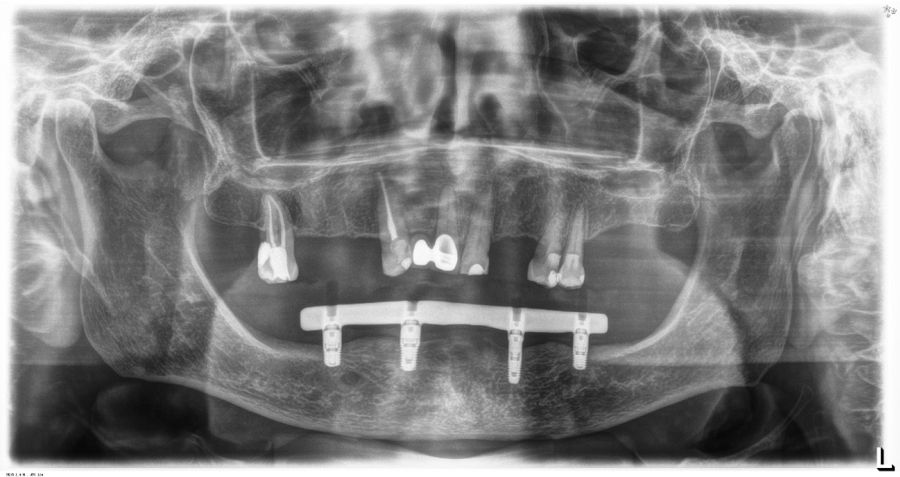

El análisis global de los 99 implantes reveló una pérdida ósea marginal media de 0,77 ± 0,26 mm en la superficie mesial y 0,79 ± 0,29 mm en la distal, valores que se mantuvieron dentro de los rangos considerados clínicamente aceptables para rehabilitaciones mandibulares. Cuando los implantes se categorizaron según su longitud, se observaron diferencias claras entre ambos grupos. Los implantes cortos (<10 mm) mostraron una pérdida ósea mesial media de 0,61 ± 0,23 mm y distal de 0,56 ± 0,22 mm, mientras que los implantes largos (≥10 mm) presentaron pérdidas significativamente mayores (mesial: 0,92 ± 0,19 mm; distal: 0,99 ± 0,17 mm). Dado que las pruebas de normalidad (Shapiro–Wilk) mostraron una distribución no normal en todos los grupos (p < 0,001), se aplicó la prueba no paramétrica de Mann–Whitney U. Los resultados confirmaron diferencias estadísticamente significativas tanto en la pérdida ósea mesial (U = 2068,5; p < 0,001) como en la distal (U = 2247,0; p < 0,005), indicando que los implantes cortos presentaron un comportamiento óseo más favorable que los implantes largos a lo largo del tiempo. Durante el tiempo de seguimiento que fue de media de 12,2 años (+/- 4,4; rango 6-23 años) no se objetivaron fracasos en ninguno de los implantes por lo que la supervivencia acumulada fue del 100%. El análisis del periodo de seguimiento mostró diferencias claras entre ambos grupos. Los implantes largos (≥10 mm) presentaron un tiempo medio de función de 14,1 ± 4,2 años (rango: 9–23 años), mientras que los implantes cortos (<10 mm) registraron un seguimiento significativamente menor, con una media de 9,8 ± 2,7 años (rango: 6–15 años). En las Figuras 3- 10 se muestran dos casos incluidos en el estudio, uno de cada situación descrita.